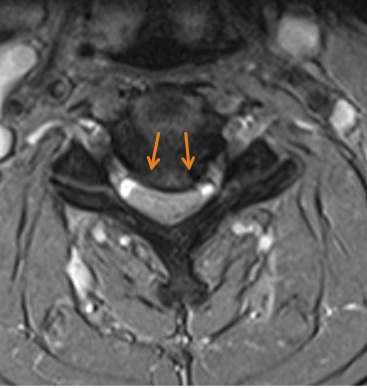

Computertomographie (CT): Halswirbelsäule mit rechts- betonter beidseitiger Foramenstenose